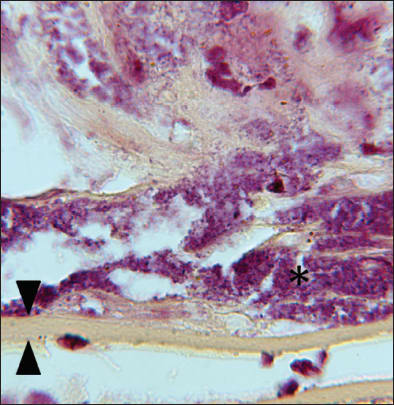

In June 2010, she returned with a visual acuity of 20/30 OS, a recurrent hypopyon and 2+ vitreous cells. A pars plana vitrectomy with intraocular lens removal was performed and intravitreal injections of vancomycin and dexamethasone were given. Histologic examination of the specimen disclosed lens capsule, cortical lens material, lens epithelium, and metaplastic fibrocellular tissue, with a moderate amount of gram-positive coccobacilli present within the tissue (Figure 2a). Cultures of the capsular bag contents in a thioglycollate broth and on anaerobic blood agar were positive for P. acnes (Figure 2b).

Figure 2a. Propionibacterium acnes organisms within the capsular bag. Brown & Hopps Gram stain, 1000x magnification. Arrowheads = lens capsule, asterisk = P. acnes organisms.